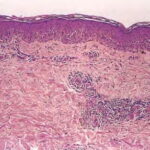

Histopathology. EM is considered the prototype of the vacuolar form of interface dermatitis . The early changes include vacuolization of the basal cell layer; tagging of lymphocytes along the dermal-epidermal junction; and a sparse, superficial, perivascular lymphoid infiltrate . Necrosis of individual keratinocytes in the basal unit occurs, which is the hallmark of EM. Because of its acute nature, there is an orthokeratotic stratum corneum. Mild spongiosis, papillary dermal edema, and extravasation of red blood cells are seen. As the lesion becomes more developed, there is a moderate lichenoid infiltrate of Iymphohistiocytes at the dermal-epidermal junction with exocytosis. More apoptotic keratinocytes within and above the basal epidermal layer are present. The |

intensity of epidermal necrosis varies from vacuolated individual keratinocytes surrounded by lymphocytes (satellite cell necrosis) at the basal unit to confluent necrosis in association with intraepidermal and subepidermal vesicles. The dermal infiltrate comprises lymphocytes and histiocytes. Eosinophils may also be present. Although one study has noted a significant number of eosinophils in drug-induced EM, this has not been noted by others. In the authors’ estimation, a generous number of eosinophils exclude EM. One study has found that an acrosyringium concentration of apoptotic keratinocytes in EM is a clue to a drug etiology . In early lesions of SJSITEN, apoptotic keratinocytes are observed scattered in the basal layer of the epidermis. In established lesions, there are numerous necrotic keratinocytes, even full-thickness epidermal necrosis, and a subepidermal bulla. The dermal inflammatory infiltrate is sparser in TEN than in EM (Fig. 9-278). Extravasated erythrocytes are commonly found within the blister cavity. Melanophages within the papillary dermis occur in late lesions. Eccrine epithelium shows a variety of changes from basal cell apoptosis to necrosis of the duct. |

In general, EM shows less epidermal necrosis, more dermal inflammation, and exocytosis, whereas SJS and TEN reveal more epidermal necrosis, less dermal inflammation, and exocytosis. However, due to the overlapping histologic features among EM, SJS, and TEN, histologic examination-while important for recognizing the spectrum of disorders-is not reliable for classifying the disease. Correlation with clinical presentation is essential. |